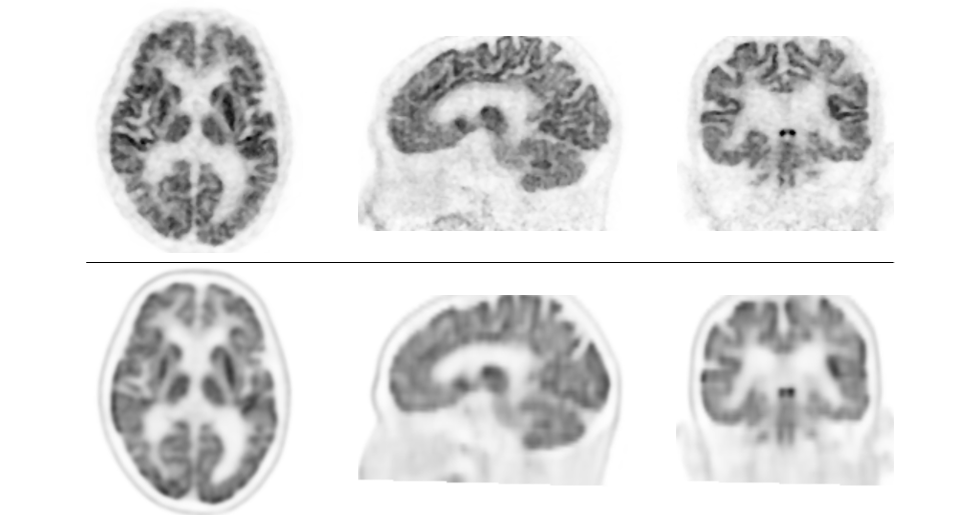

検証では、認知機能障害、てんかん等の18名の患者において、脳FDG-PET装置を用いて撮像した画像と、本PET装置で撮像した画像を比較しました。次に、認知機能障害患者17名において、従来のPET/CT装置を用いた画像と本PET装置で撮像した画像を比較しました。その結果、全例において本PET装置による画像の分解能が優れており、従来型よりも分解能が高く、細かいところまで描出できることが示されました。

また、これまで脳アミロイドPET検査においては、灰白質への集積が曖昧で、判定に苦慮する症例が約1割あるといわれてきました。今回の検証では、17例中1例の患者において、従来型PET/CT装置で、右側頭葉にアミロイド沈着が確認されました。読影指針※8 に従えば、アミロイド沈着陽性(アルツハイマー病理が存在する)と診断されるものです。しかし、本PET装置による画像では、右側頭葉を含めたどの部位にもアミロイド沈着はなく、陰性と判定され、診断が変更されることになりました。